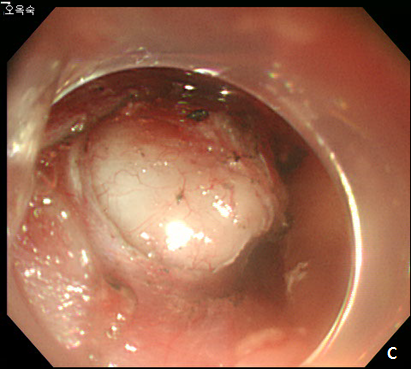

Figure 5 Submucosal tunneling endoscopic resection (STER) of esophageal subepithelial tumor (SET).

(A) Submucosal tunneling was made to approach and expose the tumor. (B) Dissection of the tumor was performed by using an insulated-tip knife. (C) After resection of the tumor, mucosal integrity was preserved as flat. (D) Entry site was sealed by using endoscopic clips.